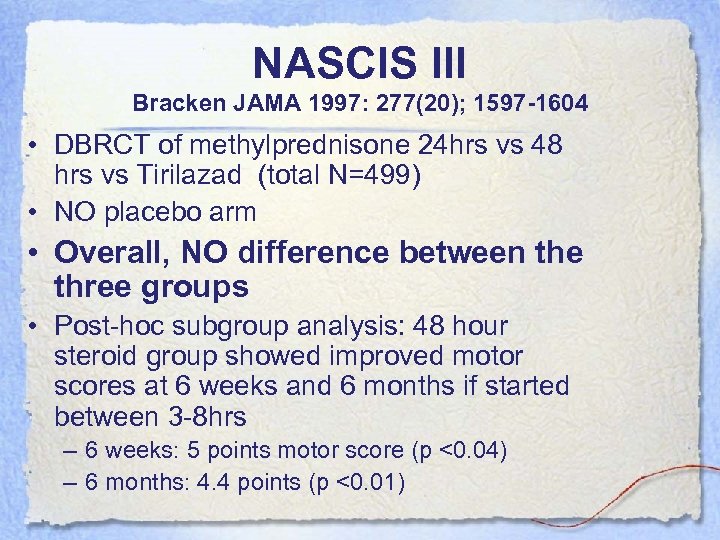

NASCIS III Bracken JAMA 1997: 277(20); 1597 -1604 • DBRCT of methylprednisone 24 hrs vs 48 hrs vs Tirilazad (total N=499) • NO placebo arm • Overall, NO difference between the three groups • Post-hoc subgroup analysis: 48 hour steroid group showed improved motor scores at 6 weeks and 6 months if started between 3 -8 hrs – 6 weeks: 5 points motor score (p <0. 04) – 6 months: 4. 4 points (p <0. 01)

NASCIS III Bracken JAMA 1997: 277(20); 1597 -1604 • DBRCT of methylprednisone 24 hrs vs 48 hrs vs Tirilazad (total N=499) • NO placebo arm • Overall, NO difference between the three groups • Post-hoc subgroup analysis: 48 hour steroid group showed improved motor scores at 6 weeks and 6 months if started between 3 -8 hrs – 6 weeks: 5 points motor score (p <0. 04) – 6 months: 4. 4 points (p <0. 01)